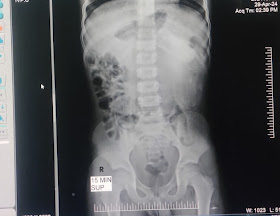

4. PRE - OP. IVU X- RAY FROM 2019.

IVU X- RAY FROM 2019.

IT WAS INITIALLY REPORTED AS A DISTAL OBSTRUCTION IN THE DISCHARGE SUMMARY, WHICH IS DATED SEPTEMBER 28, 2019 (DISCHARGE DATE: 28-09-2019).

HOWEVER A CLOSER EXAMINATION SUGGEST'S THAT THE OBSTRUCTION IS NEAR PUJ???, WHICH MAKES IT VERY CLEAR THAT IT'S NOT A DISTAL OBSTRUCTION

FURTHER EVALUATION REQUIRED.